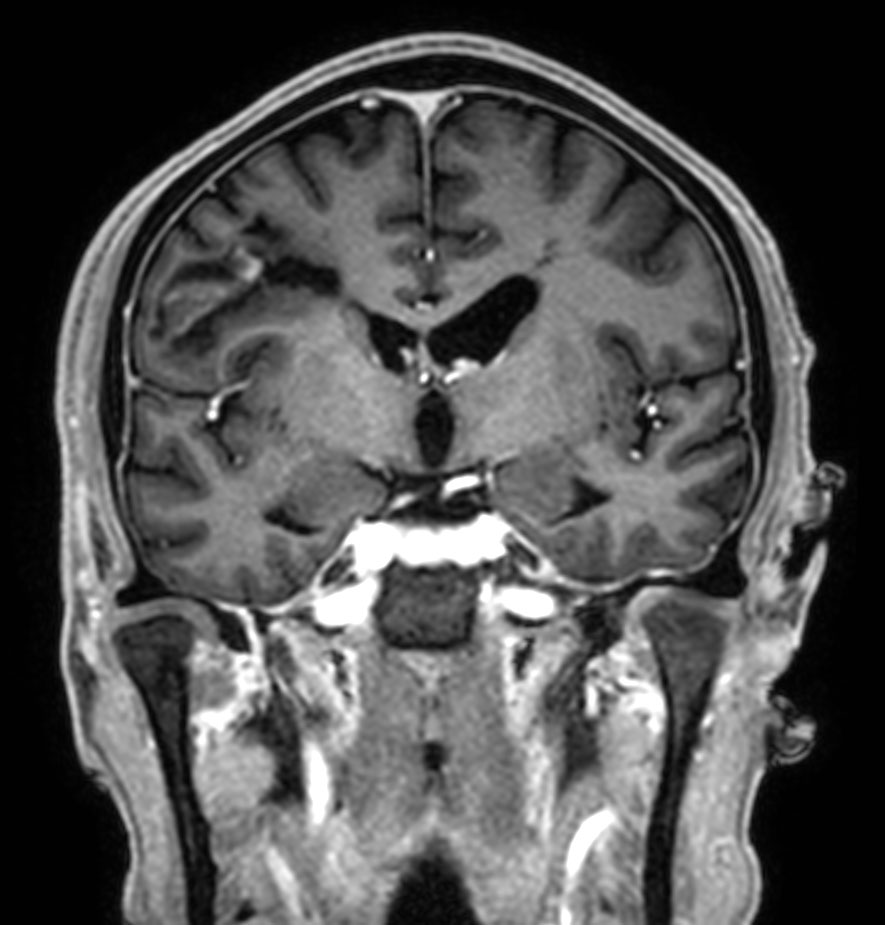

Patient with multiple brain lesions. The ExamCard includes Compressed SENSE to accelerate the entire exam and techniques for motion reduced imaging (MultiVane XD), 3D imaging to acquire high resolution data in multiple directions, 3D susceptibility weighted imaging (SWIp), DWI with EPIC Brain to bring down any residual distortion and Computed DWI to generate synthetic high b-value images.

3D T1w mDIXON XD Compressed SENSE

3D T1w mDIXON XD (reformat) Compressed SENSE